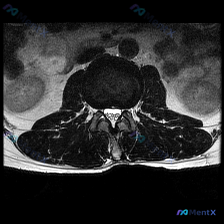

一张腰椎MRI轴位片读片:黑间盘就是椎间盘突出吗?看看分析思路

刚整理完一份腰椎MRI轴位片的读片分析,针对椎间盘病变的问题把完整思路梳理出来,和大家一起讨论。

这是一份腰椎MRI T2序列轴位图像,临床问题是评估椎间盘病变,以下是影像可见的核心表现:

- 椎间盘:该节段髓核T2信号明显减低,呈均匀低信号,也就是我们常说的「黑间盘」,提示椎间盘脱水变性;纤维环后缘没有局限性突出或游离,也没有看到后缘高信号区(HIZ)

- 硬膜囊与神经根:硬膜囊形态基本正常,受压不明显;双侧侧隐窝、椎间孔清晰,没有看到神经根受压、移位或包裹

- 椎管:前后径和横截面积都没有明显狭窄,形态完整

- 椎体与终板:椎体边缘有骨赘形成,终板没有明显Modic改变(水肿或脂肪变性)

- 韧带与小关节:双侧黄韧带轻度增厚,双侧腰椎小关节面有增生硬化,关节间隙没有明显积液